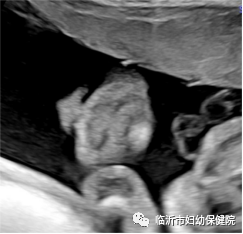

常规产前超声检查中医生问孕妈做大排畸了?“做了,在xxxx医院做的四维。”可想而知,很多很多的孕妈都把四维误认为是大排畸,认为维数越大,就越高级,非也非也。产前超声检查,包括“大排畸”是二维超声,三维、四维是在二维的基础上由计算机重建的,二维超声是平面成像,行外人士难于辨认,三维超声是立体成像,四维超声是三维超声的基础加上时间,即会动的三维,行外人士容易读懂。三维、四维超声图像是二维超声的一个辅助检查手段,对可疑异常建一步做出诊断。

#鼻唇部二维图像 >>

#鼻唇部三维图像 >>